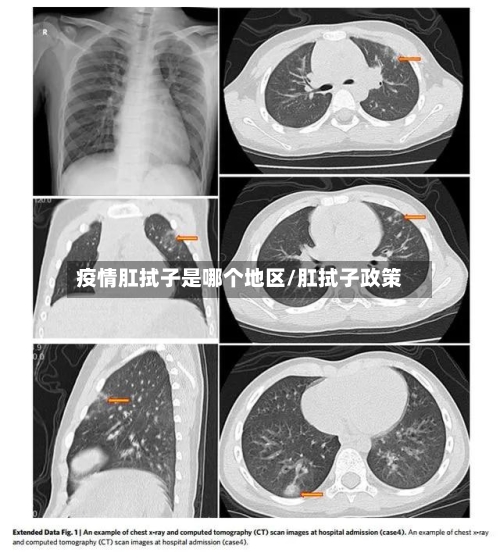

近来为尽早发现无症状感染者 ,一些地方增加了肛拭子核酸检测 。但此举能否实现提高检出率的目的,仍需进一步的科学支撑。在1月22日举行的北京新冠防控新闻发布会上,相关负责人介绍 ,对大兴区新增感染病例所在区域人员全部进行了鼻咽拭子、口咽拭子 、肛拭子及血清检测。